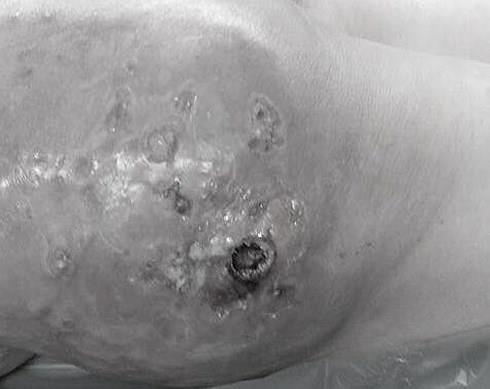

| Hình ảnh lở loét, biến dạng của nữ bệnh nhân. Ảnh: BSCC. |

Các bác sĩ của Bệnh viện Trung ương Quân đội 108 chẩn đoán bệnh nhân bị hoại tử diện rộng da, mô mỡ vùng tiêm, viêm lan toả bẹn đùi.

Bệnh nhân được mổ nạo vét khoảng 2.500 cc tổ chức hoại tử và dịch mủ.

"Với trường hợp này, điều chắc chắn là mông của bệnh nhân sẽ biến dạng", bác sĩ Lâm nhấn mạnh.